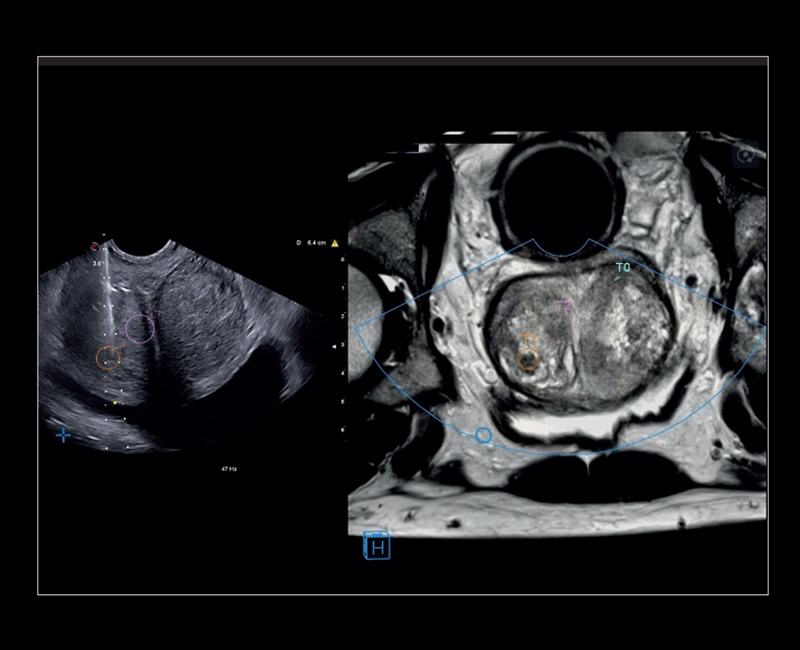

MyLab™E80 - Urofusion - TP Biopsy

MyLab™E80 - Urofusion - TP Biopsy

MyLab™X8 Platform - Prostate biopsy with Virtual Navigator fusion imaging 3D

MyLab™X8 Platform - Prostate biopsy with Virtual Navigator fusion imaging 3D

MyLab™X90 - UroFusion Automatic segmentation of the prostate MRI/US, followed by autoregistration of both modalities for targeted biopsies

MyLab™X90 - UroFusion Automatic segmentation of the prostate MRI/US, followed by autoregistration of both modalities for targeted biopsies